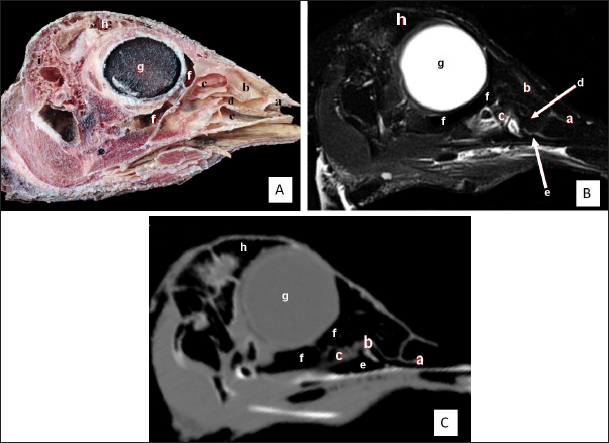

Fig. 5. Sagittal cross section of the adult ostrich head—level 4. A) Photograph of paramedian sagittal anatomical section (medial view). B) MRI and C) computed tomography images showing: a- Rostral nasal concha, b- Middle nasal concha, c- Caudal nasal concha, d- Middle nasal meatus, e- Ventral nasal meatus, f- Infraorbital sinus, g- Orbit containing eye ball, h- Frontal sinus and i- Os temporalis.

The nasal conchae exhibited in the MRI images as bright (high or hyperintense signal intensity) to gray (low or hypointense signal intensity) structures that could be divided into three parts: rostral, middle, and caudal conchae, which correlated to the morphological examinations. In contrast, the nasal conchae could not be recognized clearly on CT images compared to those obtained after MRI (Figs. 25 B and C). The paranasal sinuses with other structures could be identified using both CT and MRI. The nasal septum and paranasal sinuses revealed a white bone border (high signal intensity), soft tissue was grey (low-to-intermediate signal intensity), and they contained black gas, so both the CT and MRI scans showed little signal intensity (Figs. 15B and C and 79B, C, E, F).